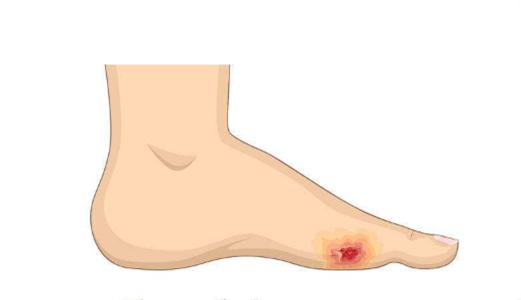

A:血栓閉塞性脈管炎最好發於下肢,表現是肢體的涼、麻、疼,到晚期可以出現靜息痛,嚴重的可以出現足趾和足潰瘍、壞疽,以及肢體的壞死,可導致截肢的風險。血栓閉塞性脈管炎可以發生全身其他臟器的血管,如腎動脈,也可以發生血栓閉塞性脈管炎。早期可以導致……

A:脈管炎最好的治療方法是絕對戒菸,防止肢體受冷。針對於比較輕的脈管炎,可以應用擴張血管的藥物治療,比如臨床上常用的前列地爾類的藥物,還有西洛他唑、安布洛克等等。如果脈管炎很重,發生了嚴重的缺血,甚至已出現肢體的潰爛、壞死,最好的治療方法是通過……

A:脈管炎的前兆取決於發生的部位和血管,如果是下肢脈管炎,早期會出現腳的溫度降低、顏色蒼白,同時有麻的感覺。進一步發展時可以出現間歇性跛行,即跛行1000米或者800米,患者會出現下肢酸脹的感覺,休息後可以緩解,早期跛行距離為800-1000米……